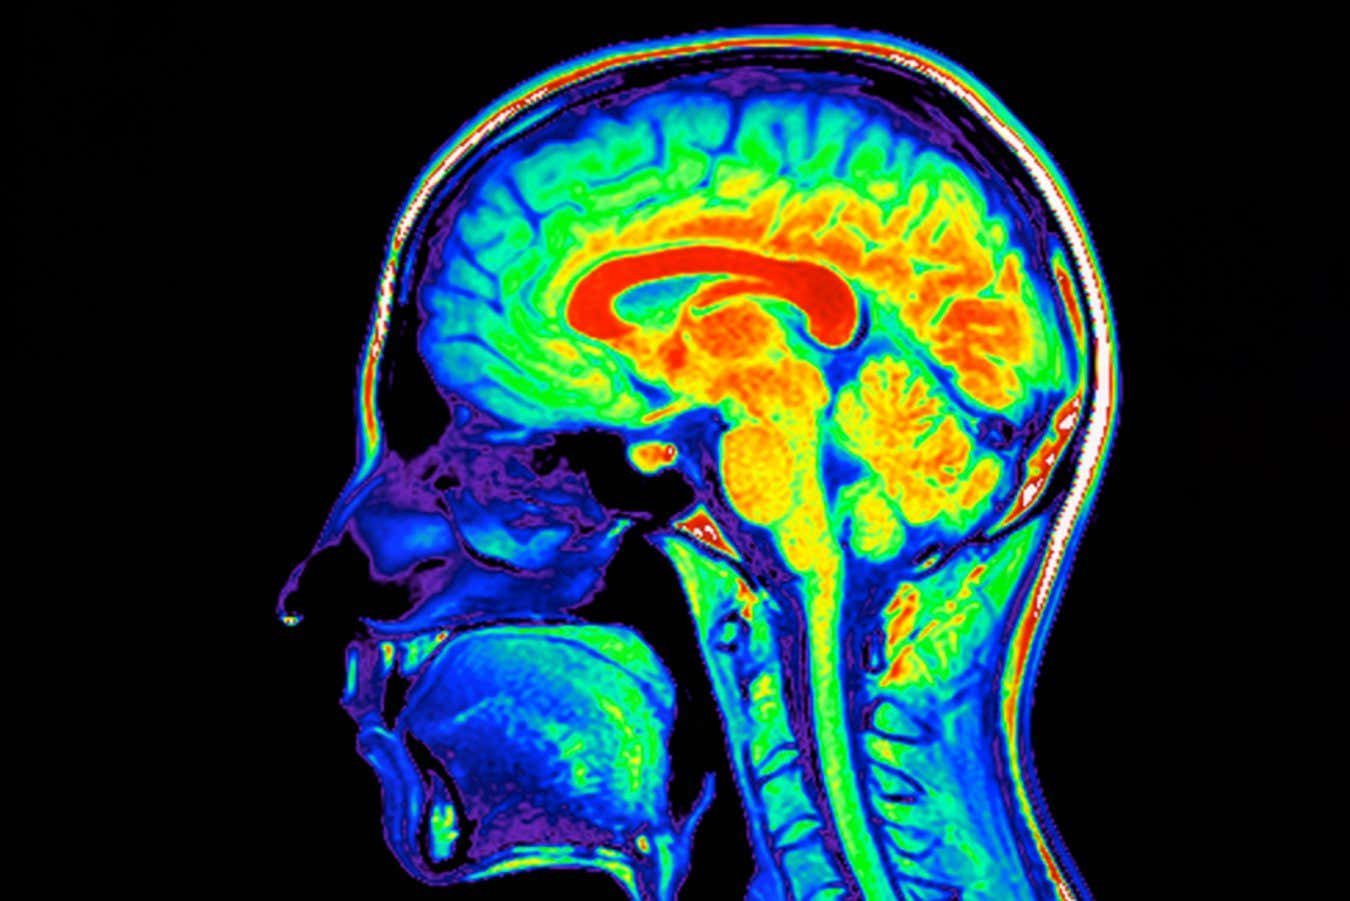

Magnetic resonance imaging scan of a human brain

Phanie/Sipa Press/Alamy